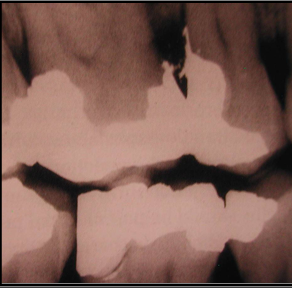

-proximal contact relation- loose contacts, uneven marginal ridges promote food trapping and create difficulty with hygiene

pontic form

A) sanitary pontic- places the convex ridge-facing surface of pontic 3mm or more away from the tissue surface

B) ridge-lap pontic- concave intaglio surface straddling the ridge, difficult to clean adequately with floss

C) modified ridge lap- slightly concave intaglio surface on the facial aspect, but the lingual aspect is convex, allowing better access for plaque removal than ridge-lap

D) ovate- completely convex intaglio surface that extends into a prepared region of the soft tissue, dental floss able to pass in all dimensions, most often used in esthetic regions of the mouth